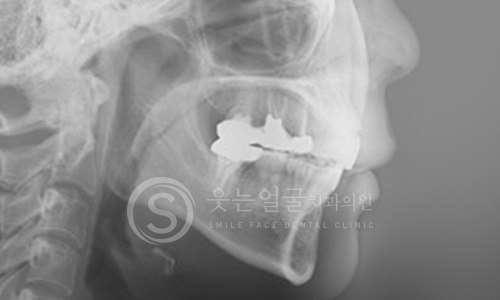

치과의사를 가르치는

강혁권 원장의 임플란트 노하우

미국 NYU 출신으로 임상 경험과 교육 경력을 겸비한

강혁권 원장의 전문 노하우로,

단순 시술이 아닌

과학적이고 체계적인 임플란트 치료를 제공합니다.